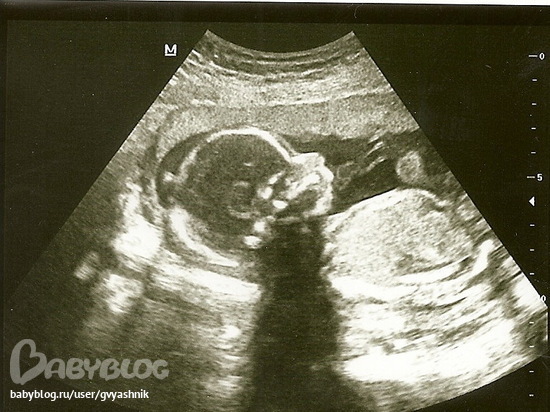

12 недель скриннинг

Муж говорит, что профиль очень "мужской")))